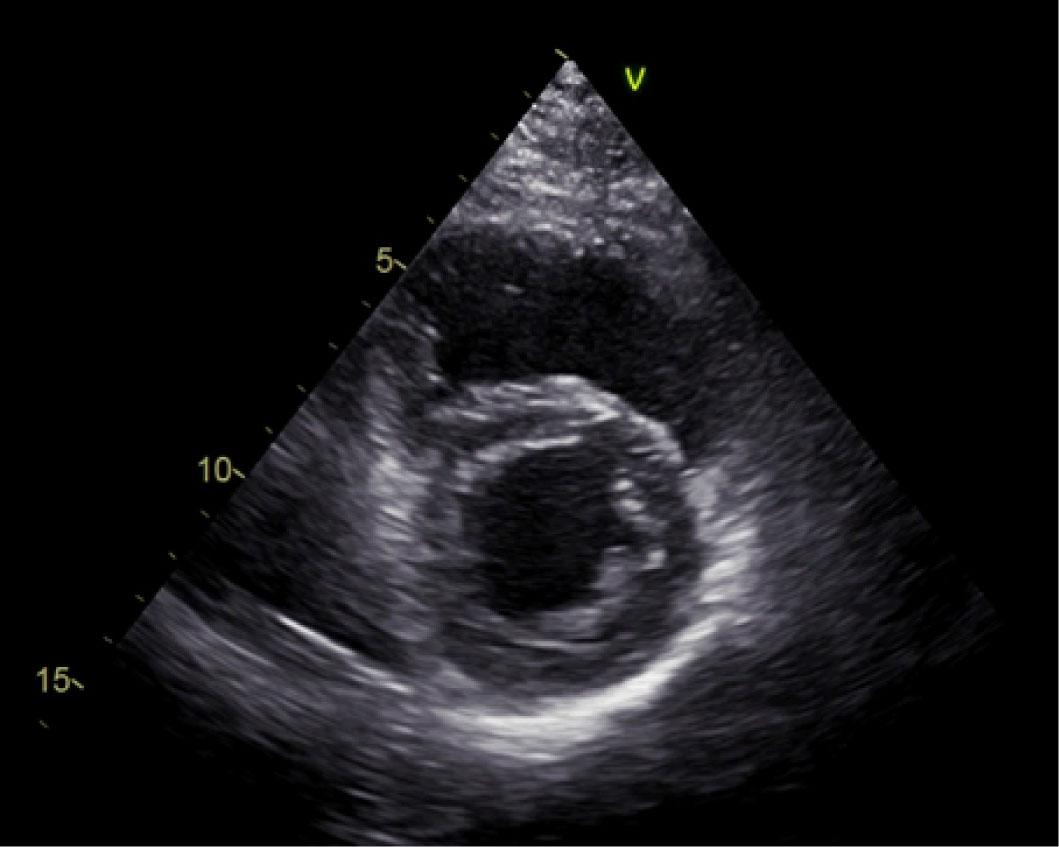

Echocardiography (Figure 1) showed moderate concentric hypertrophy of the left ventricle (LV mass index 143 g/m2, interventricular septum diastolic thickness 15 mm, posterior wall diastolic thickness 13 mm, with trabeculations at the level of the lateral wall from the middle third to the apex), diffuse hypokinesia of the LV walls, global LV systolic dysfunction, LV ejection fraction (LVEF) 30%, grade III diastolic dysfunction, increased filling pressures, dilated left atrium (left atrium volume 48 ml/m2), slightly enlarged right ventricle with systolic dysfunction, tricuspid S wave velocity determined by tissue Doppler imaging technique 0.12 m/s, moderate functional mitral regurgitation, moderate functional tricuspid regurgitation, and high probability of arterial pulmonary hypertension.

Two-dimensional parasternal short axis echocardiography (end-systolic frame)—note the thickness of the lateral wall, which appears trabeculated